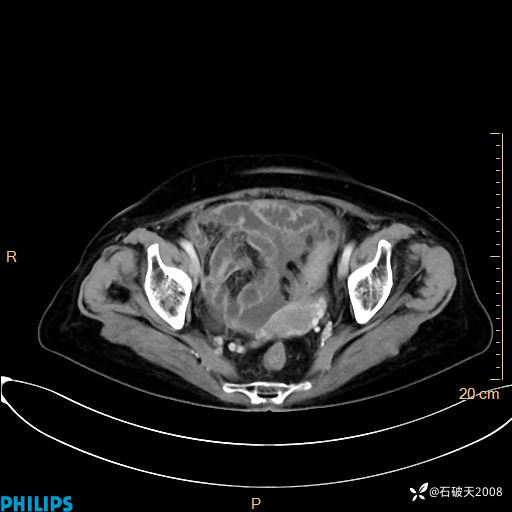

静脉期